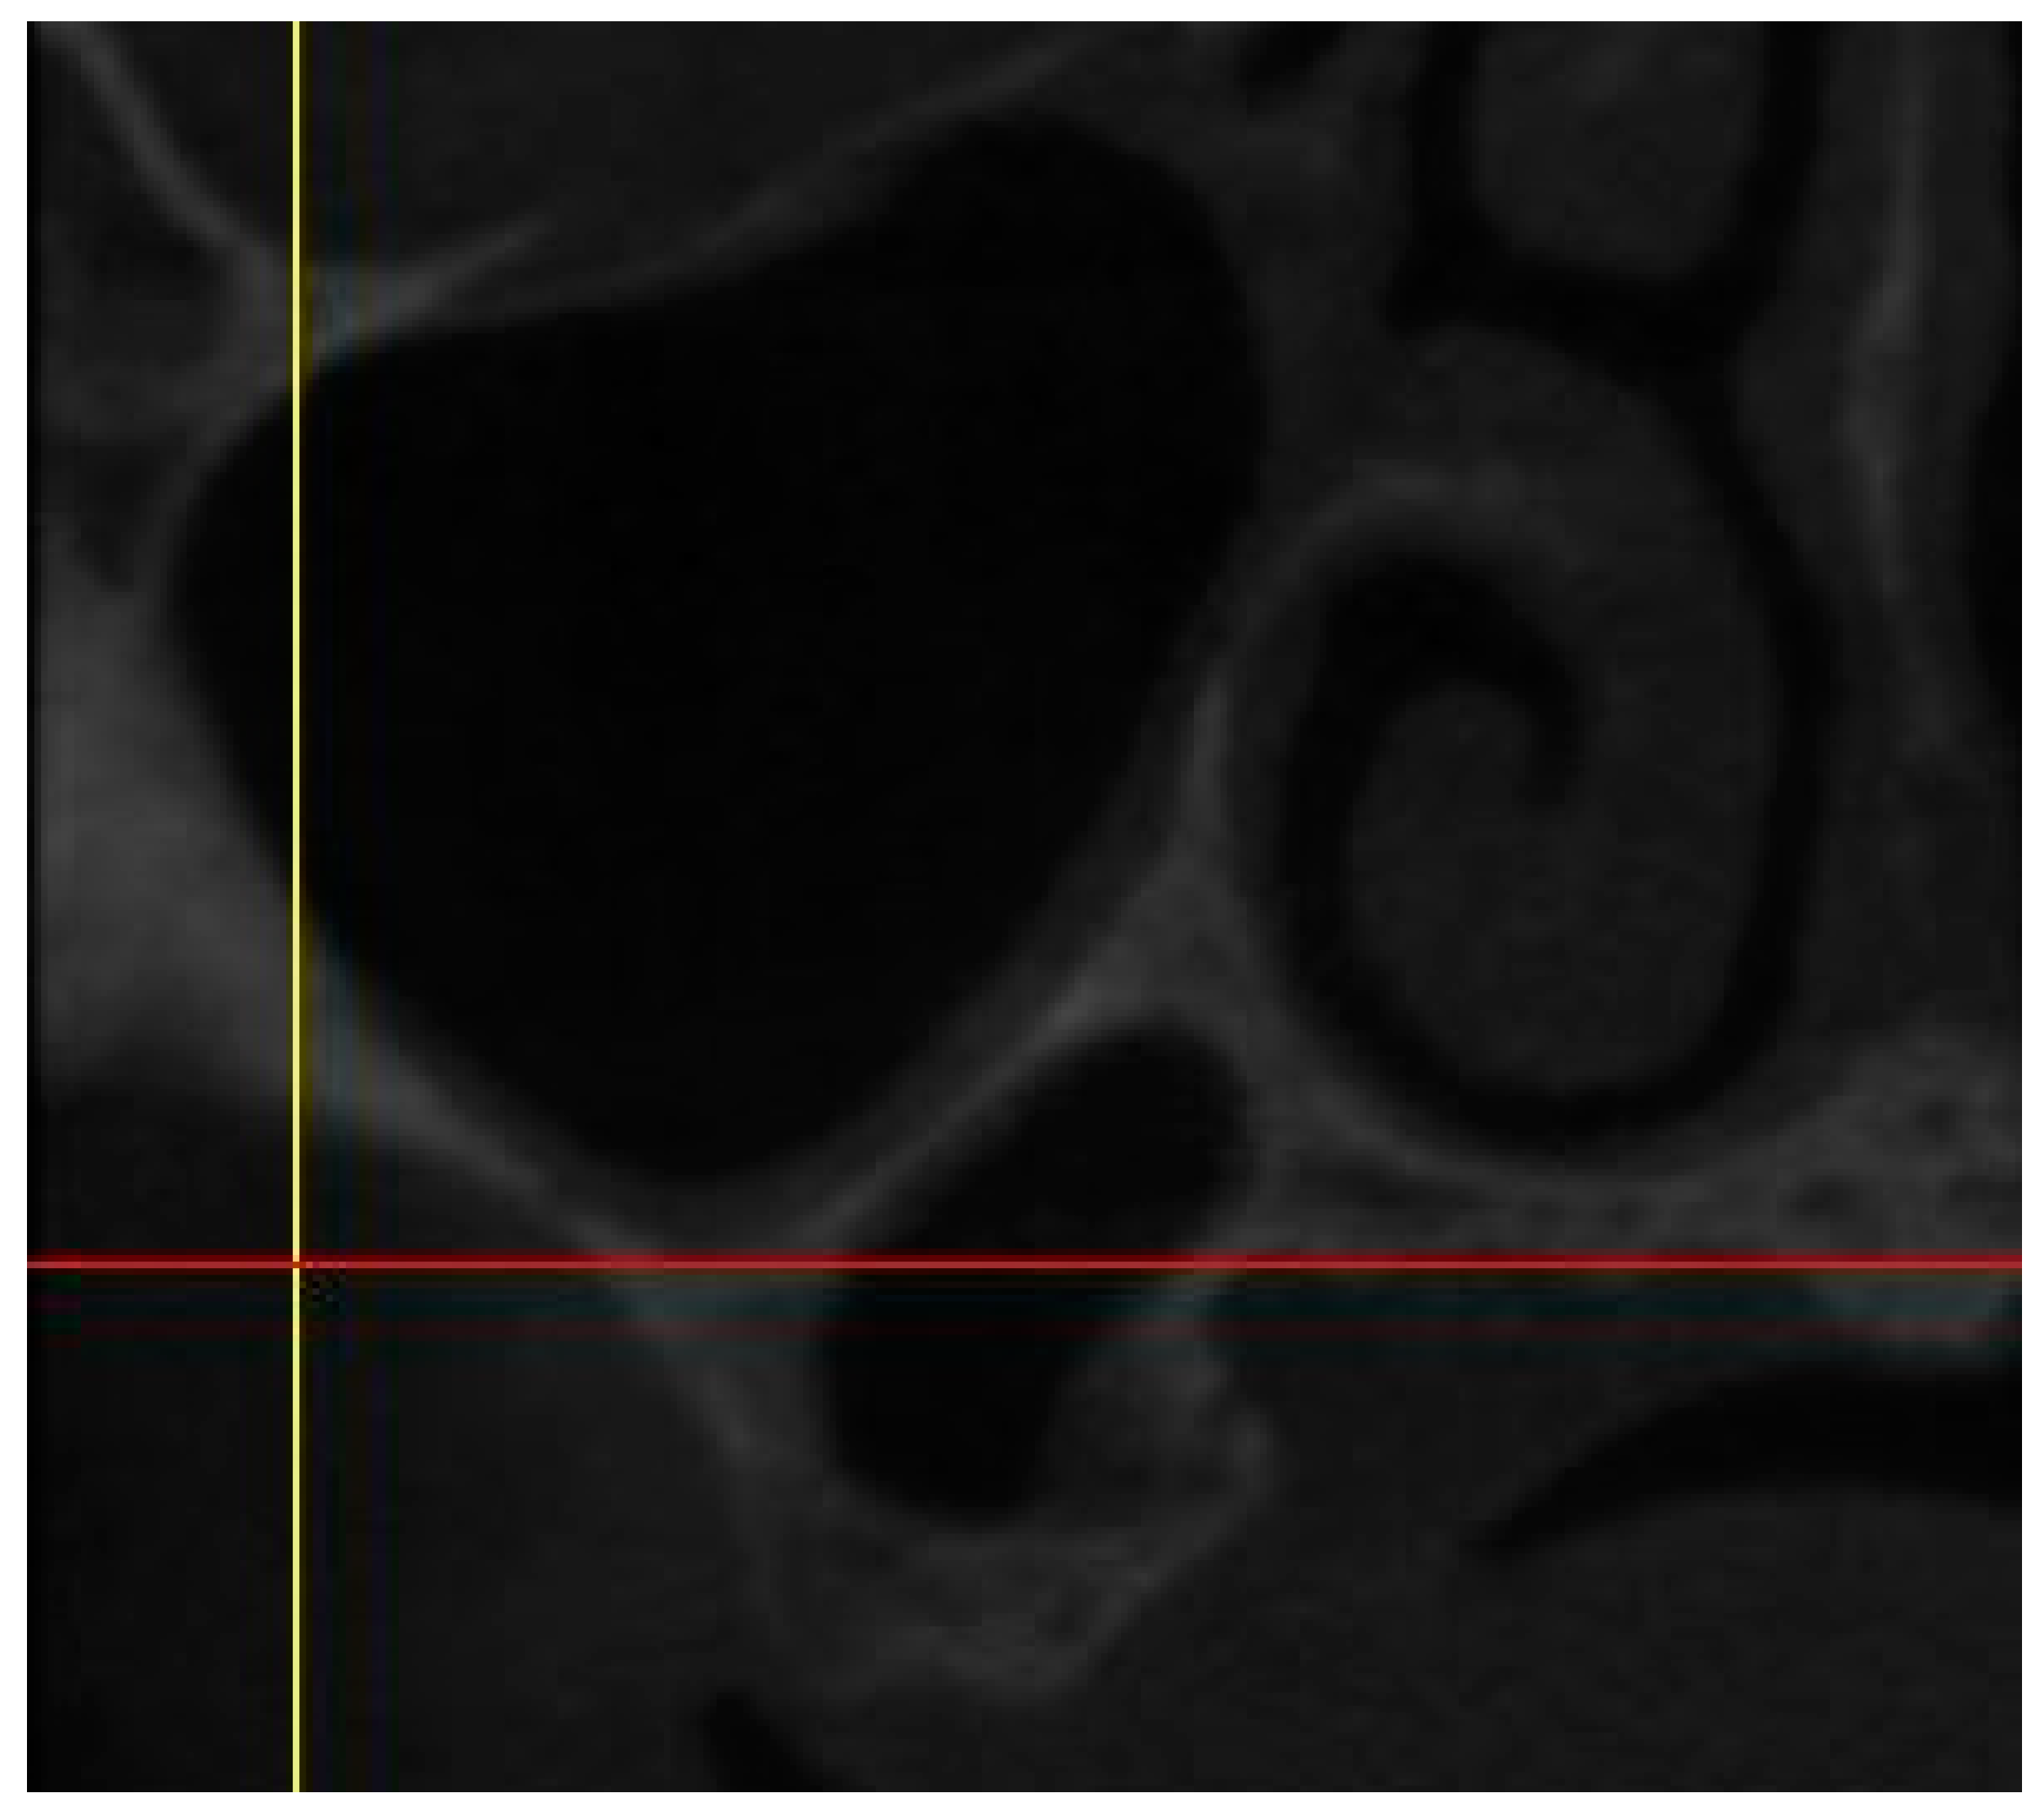

• Residual anterior and posterior ridge heights and widths (maxillae and mandible). (Figure 1)

Distances were calculated from the crest of the ridge. In case of thin ridge crest, alveoplasty was assumed and measurements were taken from the widest area that would accommodate the implant diameter. The alveoplasty was no more than 5mm. The measurements were taken from the crest if more than 5mm alveoplasty is needed, and the site was noted for grafting.

The width was calculated 1-2mm apically from the height start point.

Figure 1. CBCT Image showing height and width measurement calculation.